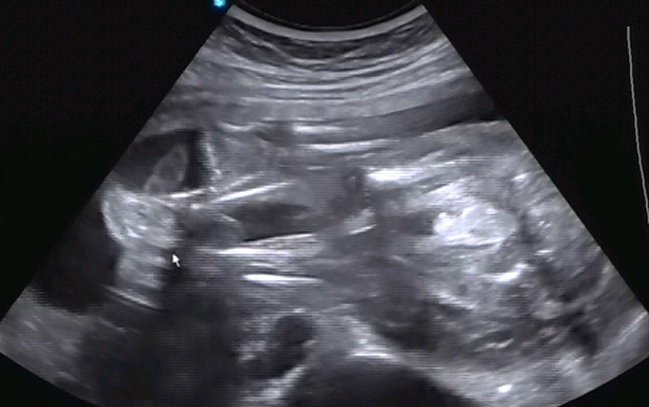

Пол малышаДевочки,посмотрите...ну это же мальчик????

У меня живот всегда острый, все никаких полосок, все беременности разные так что фигня все эти приметы =) А на УЗИ у вас явно мужик =)

Писюн же торчит))) наоборот слышала на пацанов живот острый) а мне и с дочей говорили по приметам ,что сын и с сыном , что на сына похоже) просто я с токсом худею и хорошею, плюс не курю, лицо свежеет. Плюс форма живота видимо такая, вперед растет, даже когда полнею всегда талия остается. Ну и в лице не меняюсь, нос не пухнет и пигментации нет, обычно такое на девочек говорят.

ой,не обращайте внимания))))там же у вас виден пистолетик мальчугана)